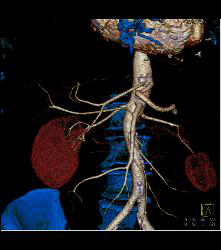

Right Hepatic Artery Arises Off the Superior Mesenteric Artery (SMA) and Left Hepatic Artery Arises Off the Aorta